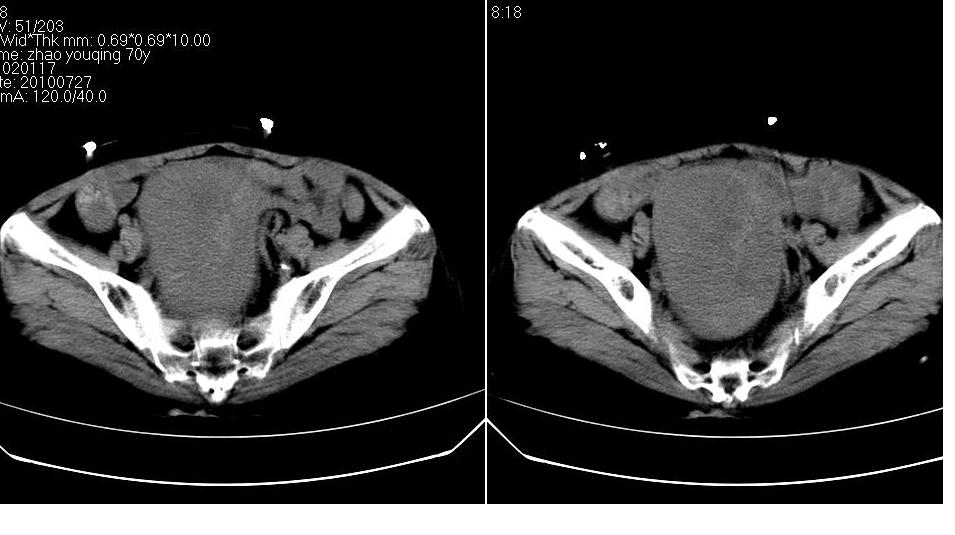

女,70岁,十天前在上级医院确诊宫颈癌,具体病史不详。

子宫形态增大,其内密度不均匀,宫颈部未见异常

子宫形态增大,其内密度不均匀,宫颈部未见异常,建议增强。

子宫体积增大,其内密度不均,考虑子宫内膜癌侵犯宫颈

宫颈癌阻塞性宫腔积液?累及宫腔?

子宫增大可以是肌瘤的改变,宫颈癌多为鳞癌,子宫内膜癌多为腺癌。